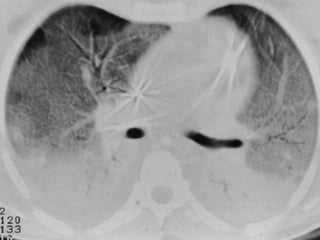

• Comparado a dados tomográficos os critérios

AECC são de baixa sensibilidade (84%) e

sensibilidade (51%)

DEFINIÇÕES DE BERLIM

• Raio X do tórax:

▫ Opacidades bilaterais não explicáveis por efusões,

atelectasias ou nódulos